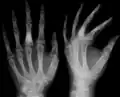

-

X-ray showing calcified enchondromas localized in finger a 37-year-old patient affected with Ollier disease -

X-ray showing enchondromas localized in the humerus of a 37-year-old patient affected with Ollier disease -

X-ray showing enchondromas localized in the lower part of the radius of a 37-year-old patient affected with Ollier disease -